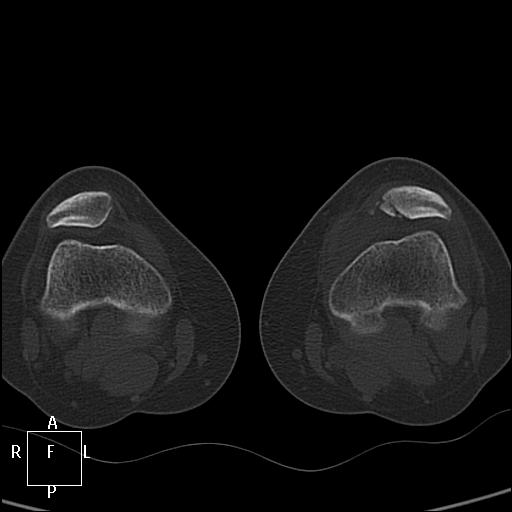

КТ коленных суставов. Травма. Женщина 31г

Наша врач, травма была в понедельник, подскользнулась и подвернула ногу, "думала, что пройдёт". Предыдущая травма в ноябре. Сейчас шикарный кровоподтек по внутренней стороне голени.

Публикации: 1749

А не могёт это быть варианом строения надколенника, в том смысле не ужели можно подвернув ногу (без удара) разорвать надколенник , как мне увиделось только суставная поверхность повреждена..??А кровоподтек от разыва связок.. хотя скиалогически подумал бы о переломе.. Или это неполный перелом на фоне аномалии..

Особый вариант перелома – вертикальный, при котором линия перелома проходит сверху вниз. В подавляющем большинстве случаев такие переломы не смещаются, так как тяга мышцы направлена снизу вверх, то есть вдоль линии перелома.   ( http://travmaorto.ru/103.html )

Скорее всего при подвороте стопы произошел отрыв медиальной связки надколенника. http://www.sportmedicine.ru/knee_norm.php

При вывихе надколенника кнаружи происходит отрыв медиального связочного аппарата, иногда с фрагментом надколенника. А вывих вправляется самостоятельно.